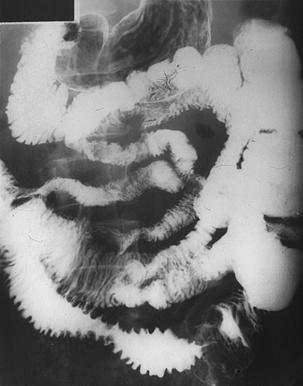

疾病(病理主体)的分类恶性淋巴系肿瘤/恶性淋巴瘤

部位(按器官分)小肠/其他

检查方法X线

肿瘤最大直径40以上

多发性肿瘤(同一器官)有(同时性)